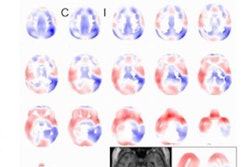

Icometrix's icobrain ep software uses AI algorithms to facilitate the detection of subtle cortical abnormalities on the brain MR images of epilepsy patients. The software provides a quantitative report on brain asymmetry that indicates whether a patient has intractable -- or uncontrollable -- epilepsy, which is overlooked in as much as 45% of cases examined using traditional image evaluation, the company said.